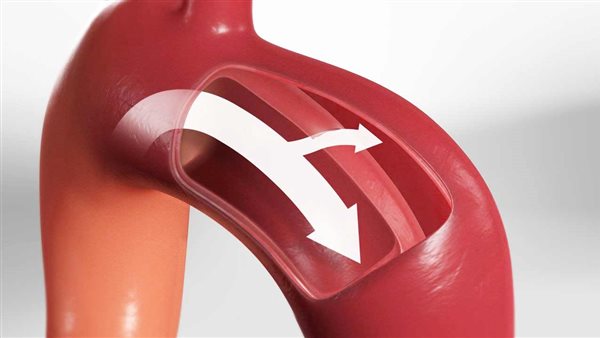

- بالإضافة إلى أنه من المحتمل أن يتضرر الصمام الأورطي فيما يعرف بارتجاع الصمام الأورطي، أو تهتك النسيج المبطن المحيط بالقلب فيما يعرف بالاندحاس القلبي.

ولمن يرغب في معرفة إجاية سؤال ما هو إنسلاخ الشريان الأورطي؟، يوضح أخصائي أمراص الباطنة والقلب والصدر، أن انسلاخ الشريان الأورطى يعد من الحالات الطبية الخطيرة والتي تصيب الطبقات الداخلية للشريان؛ حيث تنسلخ تنفصل الطبقة الداخلية عن الطبقة الوسطى للشريان؛ نتجو تراكم الدم بينهما، منبهًا إلى قد يسبب الوفاة في حال انفجر الشريان.